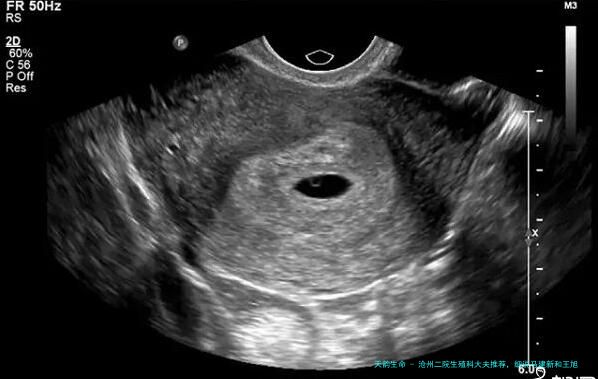

沧州市二医院生殖科的马建新医生看女性不孕都比较好,而该生殖医学科看男性不育相较好的医生就是王旭初医生,这两位医生都擅长辅助生殖助孕技术,是沧州中西医结合医院试管医生中比较富有经验的,技术都比较娴熟,助孕的成功率也比较高。所以说,所有人选择沧州市二医院生育科的医生实际上依照本人的病情,以及医生诊治的特长来相应选择就好。

师从中国第一个例子试管婴儿创造者张丽珠教授,全国有名泌尿男科专业人士潘天明教授。2002年四月发展了沧州市首个案例经阴超卵泡穿刺助孕术,并获临床妊娠成功。2003年三月开展试管婴儿实践室职业,获沧州市首例试管婴儿临床妊娠成功。2004年二月成功开展沧州市第一例多胎妊娠减胎术,成功为一例四胞胎患者减为孪生儿,分娩一双龙凤胎。2005年完成市级立项研究课题“多囊卵巢综合征合并不孕症系列研究“,获沧州市科技前行二等奖。